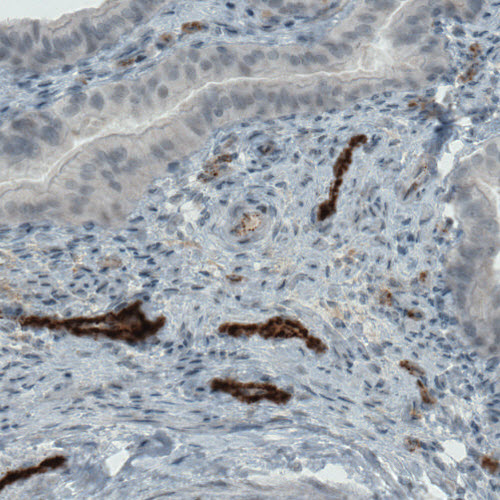

Immunohistochemical staining of human rectum shows strong immunoreactivity in a blood vessel.